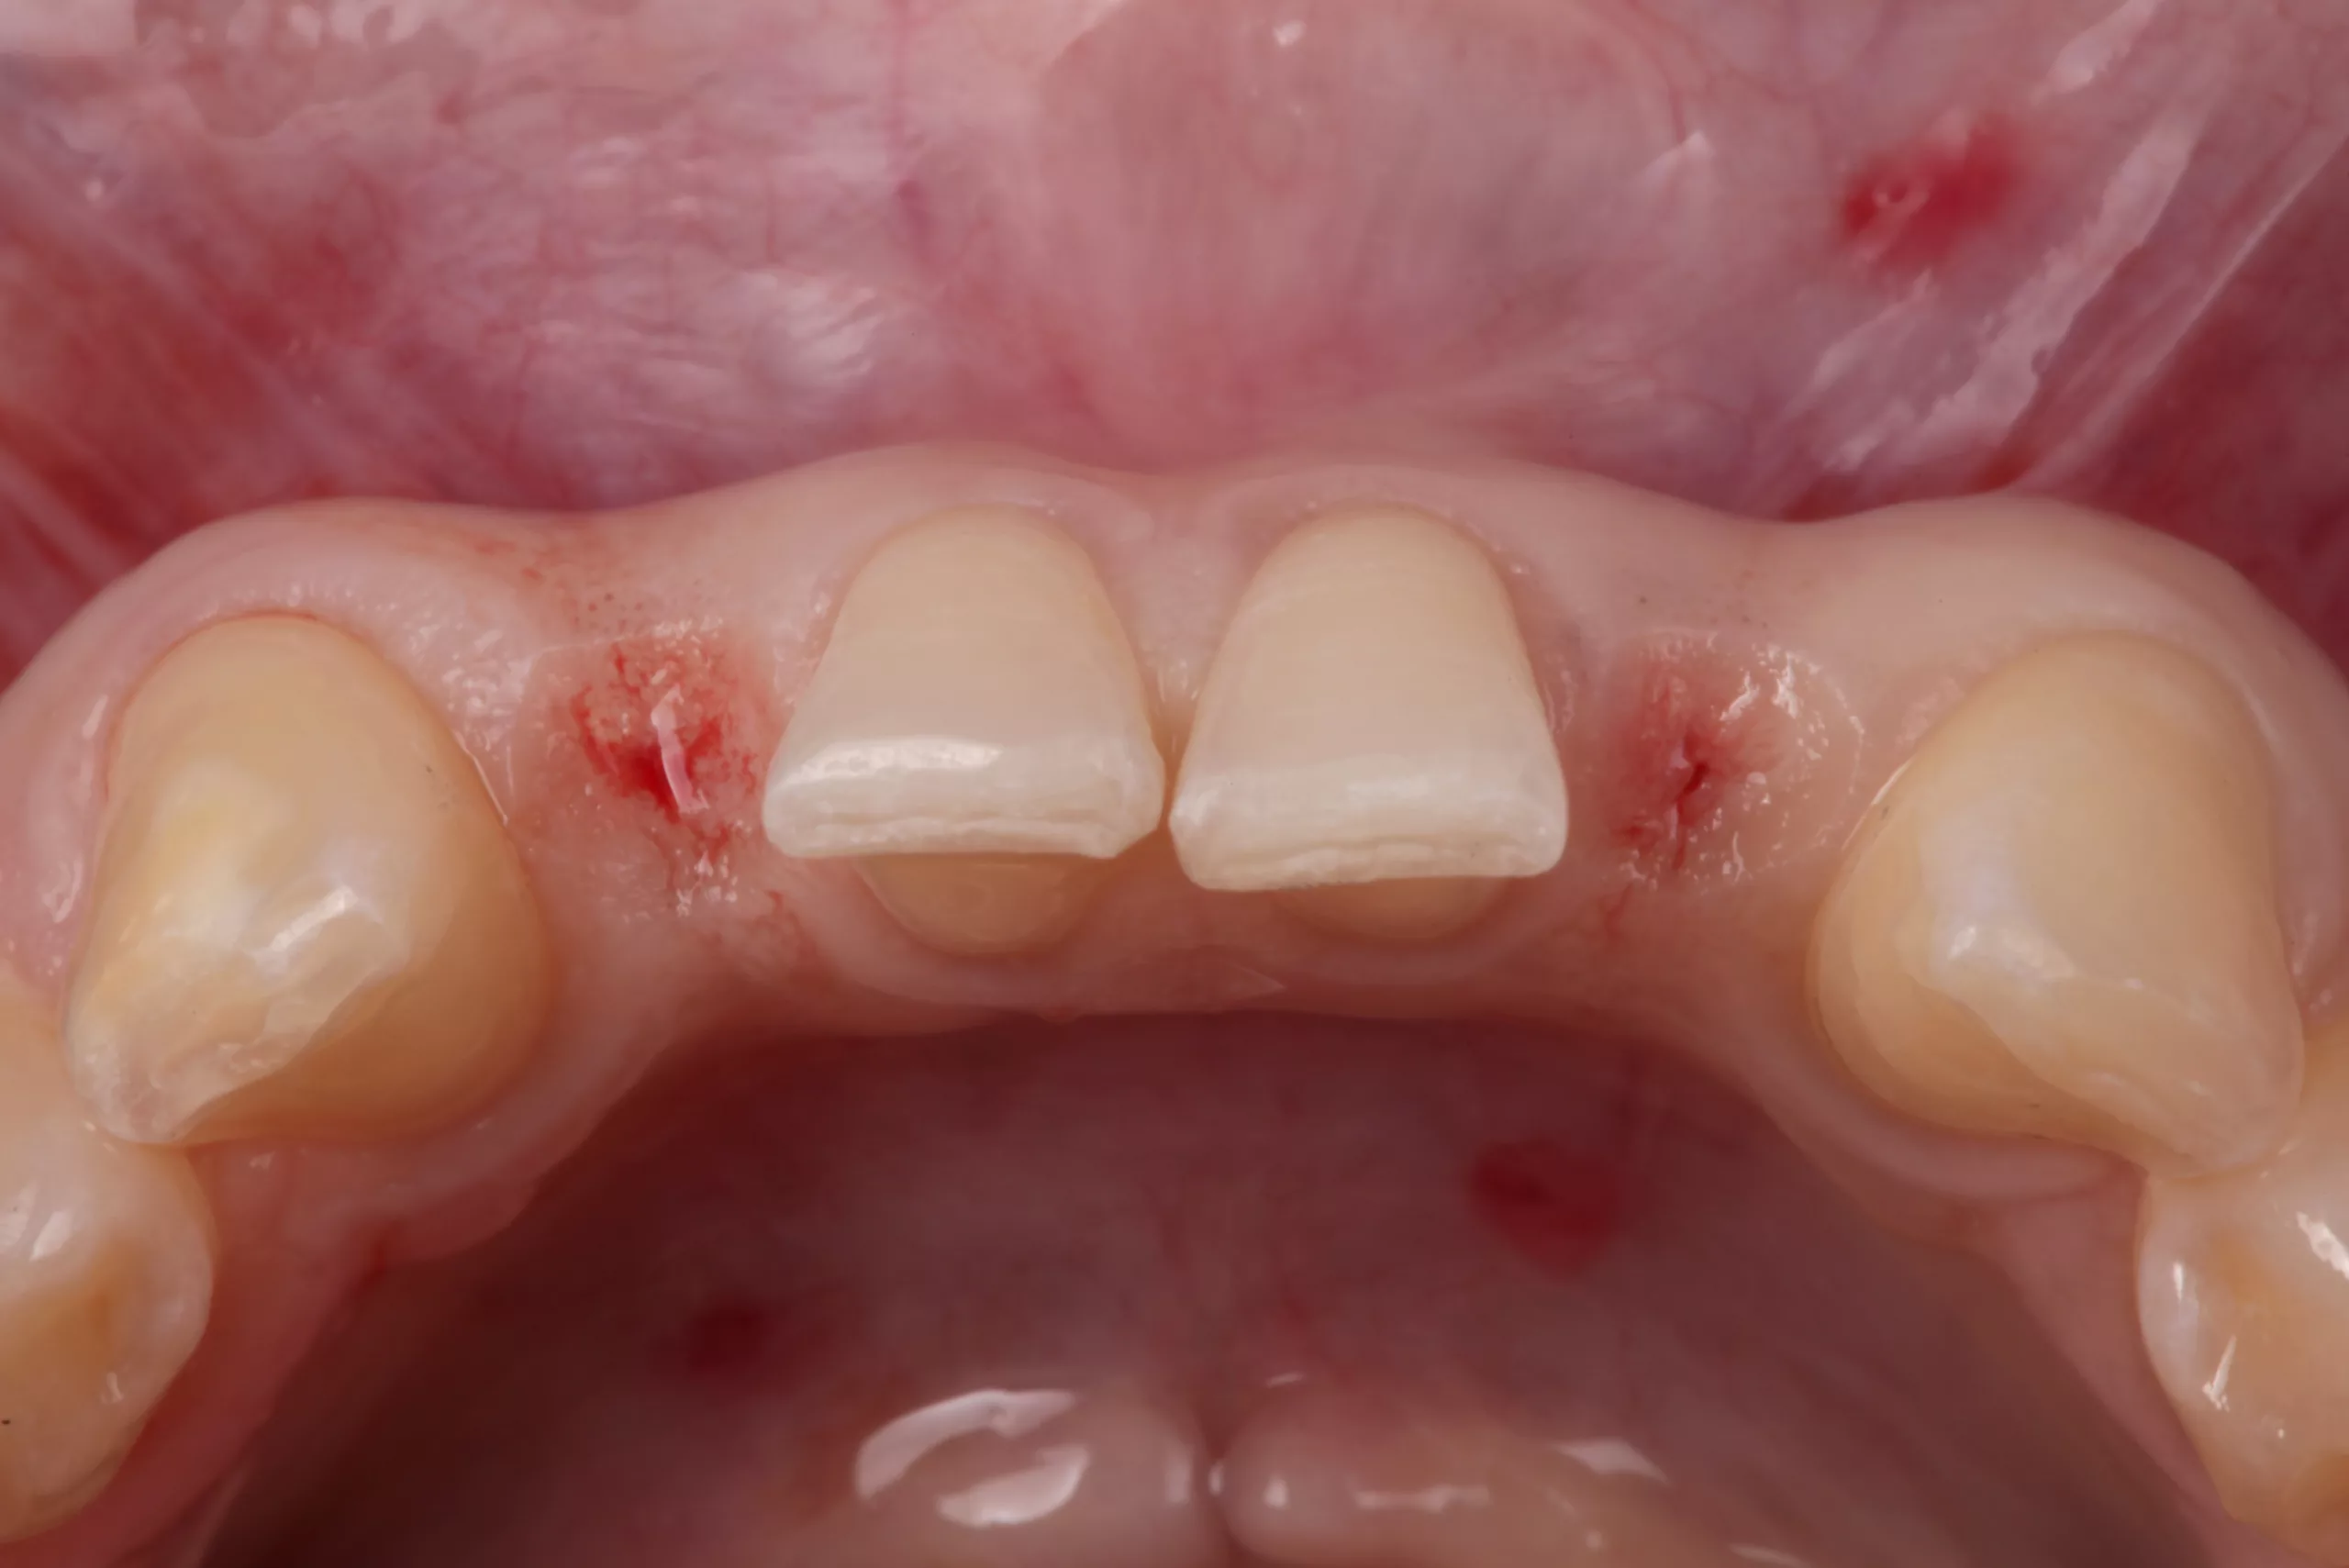

Im Anschluss an die Präparation findet die Pontic-Ausformung statt (Abb. 7). Im Idealfall steht ausreichend Gewebe in vertikaler und horizontaler Ausdehnung zur Verfügung und eine forcierte Ausformung mit einer grob diamantierten Kugel, einem Elektrotom oder dem Laser reicht aus. Bei wenig Gewebe im basalen Bereich des Brückengliedes sollte eine chirurgische Vorbehandlung im Rahmen der präprothetischen Vorbehandlung (z. B. Rolllappen, Bindegewebstransplantat) in Erwägung gezogen werden.

Okklusion und Artikulation können nun überprüft und ggf. angepasst werden. Abschließend folgt die Instruktion des Patienten zur effizienten Reinigung im Bereich der Adhäsivbrücke. Eine Situationsabformung mit anschließendem Situationsmodell und die fotografische Dokumentation des klinischen Ergebnisses helfen bei den Nachsorgesitzungen zur Kontrolle etwaiger Veränderungen der Pfeilerzahnstellung (Abb. 13- 15).